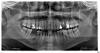

cent01 Опубликовано 13 мая, 2009 Автор Поделиться Опубликовано 13 мая, 2009 Вот tiff-файл панорамного снимка. Удаленный зуб - сверху слева шестой от центра или третий от левого края.Подробный снимок сблизи так и не дали, оказывается Ссылка на комментарий

cent01 Опубликовано 13 мая, 2009 Автор Поделиться Опубликовано 13 мая, 2009 Не загрузилось, так как размер был больше метра. Вот, оптимизированное изображение jpg, размер 0.5 мб К сожалению, на этом рисунке этот зуб не виден подробно. Завтра пожалуй схожу за снимком именно того зуба. Ссылка на комментарий

Dr. Surkin Опубликовано 13 мая, 2009 Поделиться Опубликовано 13 мая, 2009 на зубе киста приличная была - однозначно удалять. Там еще есть что подергать. и парадонтитище махровый! Fury, а вы откуда знаете? Это что , видно на снимке? Конечно видно. Ссылка на комментарий

cent01 Опубликовано 13 мая, 2009 Автор Поделиться Опубликовано 13 мая, 2009 (изменено) Спасибо.Вот я обвел удаленный зуб - а то может поймут неправильно (слева - по рисунку, а не лицу. Если по лицу - то слева торчит реально конченный зуб)http://s61.radikal.ru/i174/0905/1e/726322f2998c.jpg http://s61.radikal.ru/i174/0905/1e/726322f2998c.jpg Изменено 13 мая, 2009 пользователем cent01 Ссылка на комментарий

доминика Опубликовано 14 мая, 2009 Поделиться Опубликовано 14 мая, 2009 (изменено) Вот фотографии двух зубов, кандидатах на удаление. Что здесь можно предпринять, чтобы сохранить их? да снимки -то вверху есть 25 ,однозначно на выход ,26 карманы приличные-смысла перелечивать каналы нет Изменено 14 мая, 2009 пользователем доминика Ссылка на комментарий